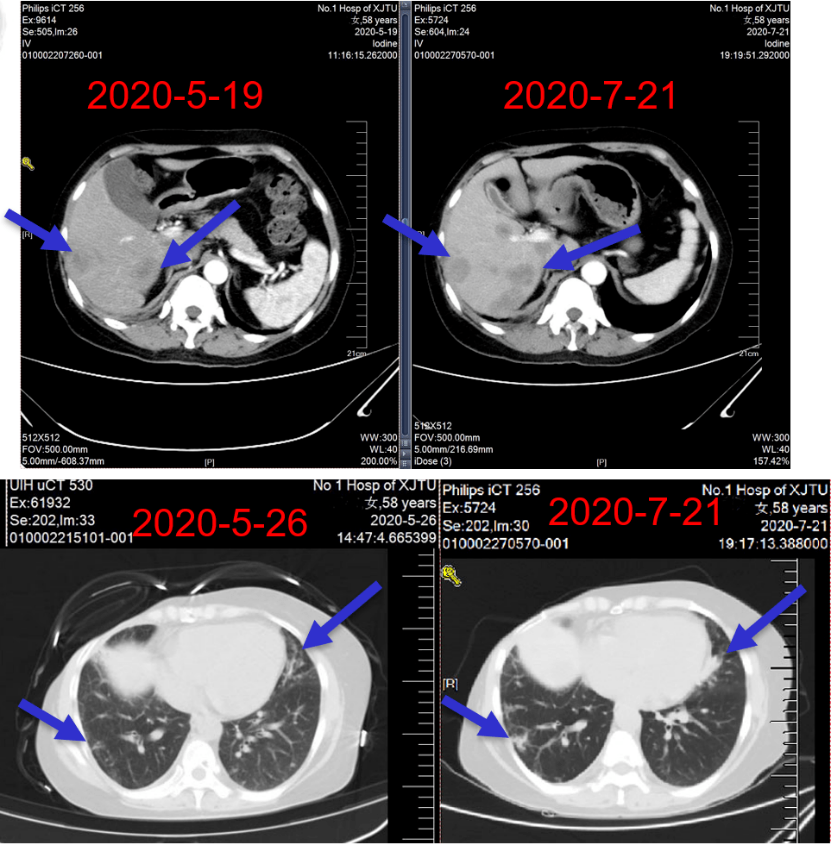

图9:二线治疗期间随访肺部CT

图10:二线治疗期间随访颅脑CT

图11:二线治疗期间随访肝脏CT

病情演变:2020年5月患者出现发热,反复发作,最高38.5℃。

2020年7月23日~2020年10月16日,给予艾立布林(2 mg,d1,d8,q3w)×5周期抗乳腺癌治疗。

肺、肝脏转移病灶治疗2周期后部分缓解(PR),4周期后 SD。

图14:四线治疗期间随访肺部CT

图15:四线治疗期间随访肝脏CT